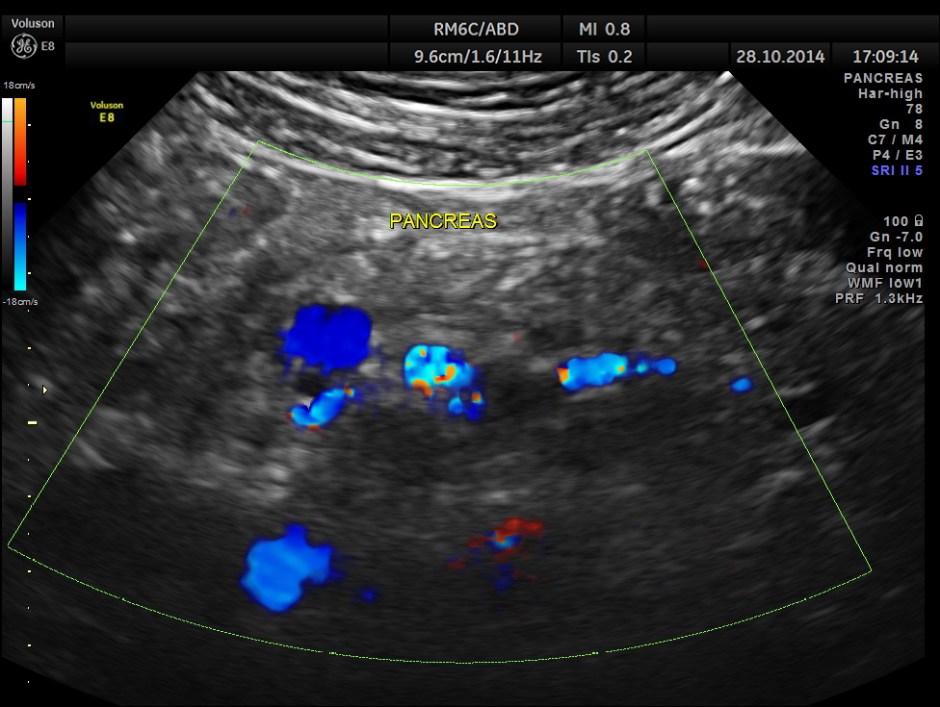

Colour flow imaging of the same

Main portal vein show flow reversal ( blue colour ) – centri-fugal flow suggestive of portal hypertension.

Epigastric varices are also seen.